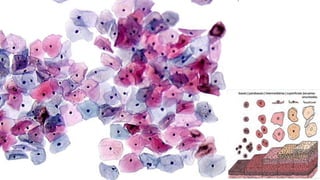

Células Escamosas

Trofismo do Epitélio

Epitélio Hipertrófico Epitélio HipotróficoEpitélio Normotrófico Epitélio Atrófico